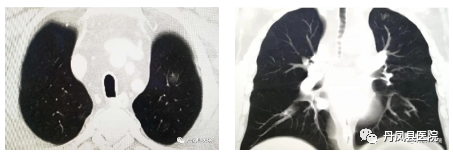

肺动脉CTPA

肺动脉CTPA诊断肺栓塞的敏感性可达75%~100%,特异性可达80%~100%,对于叶、段动脉显示准确性更高,有助于明确肺动脉内栓子的位置、范围、程度及肺动脉血流动力学状态等。